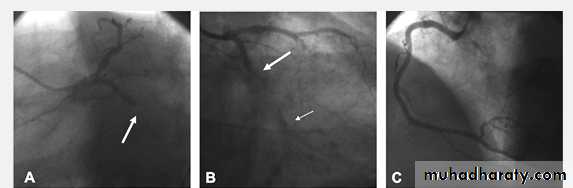

Severe proximal LAD Lesion

CVS

Very severe proximal LAD stenosis

Total CX Occlusion